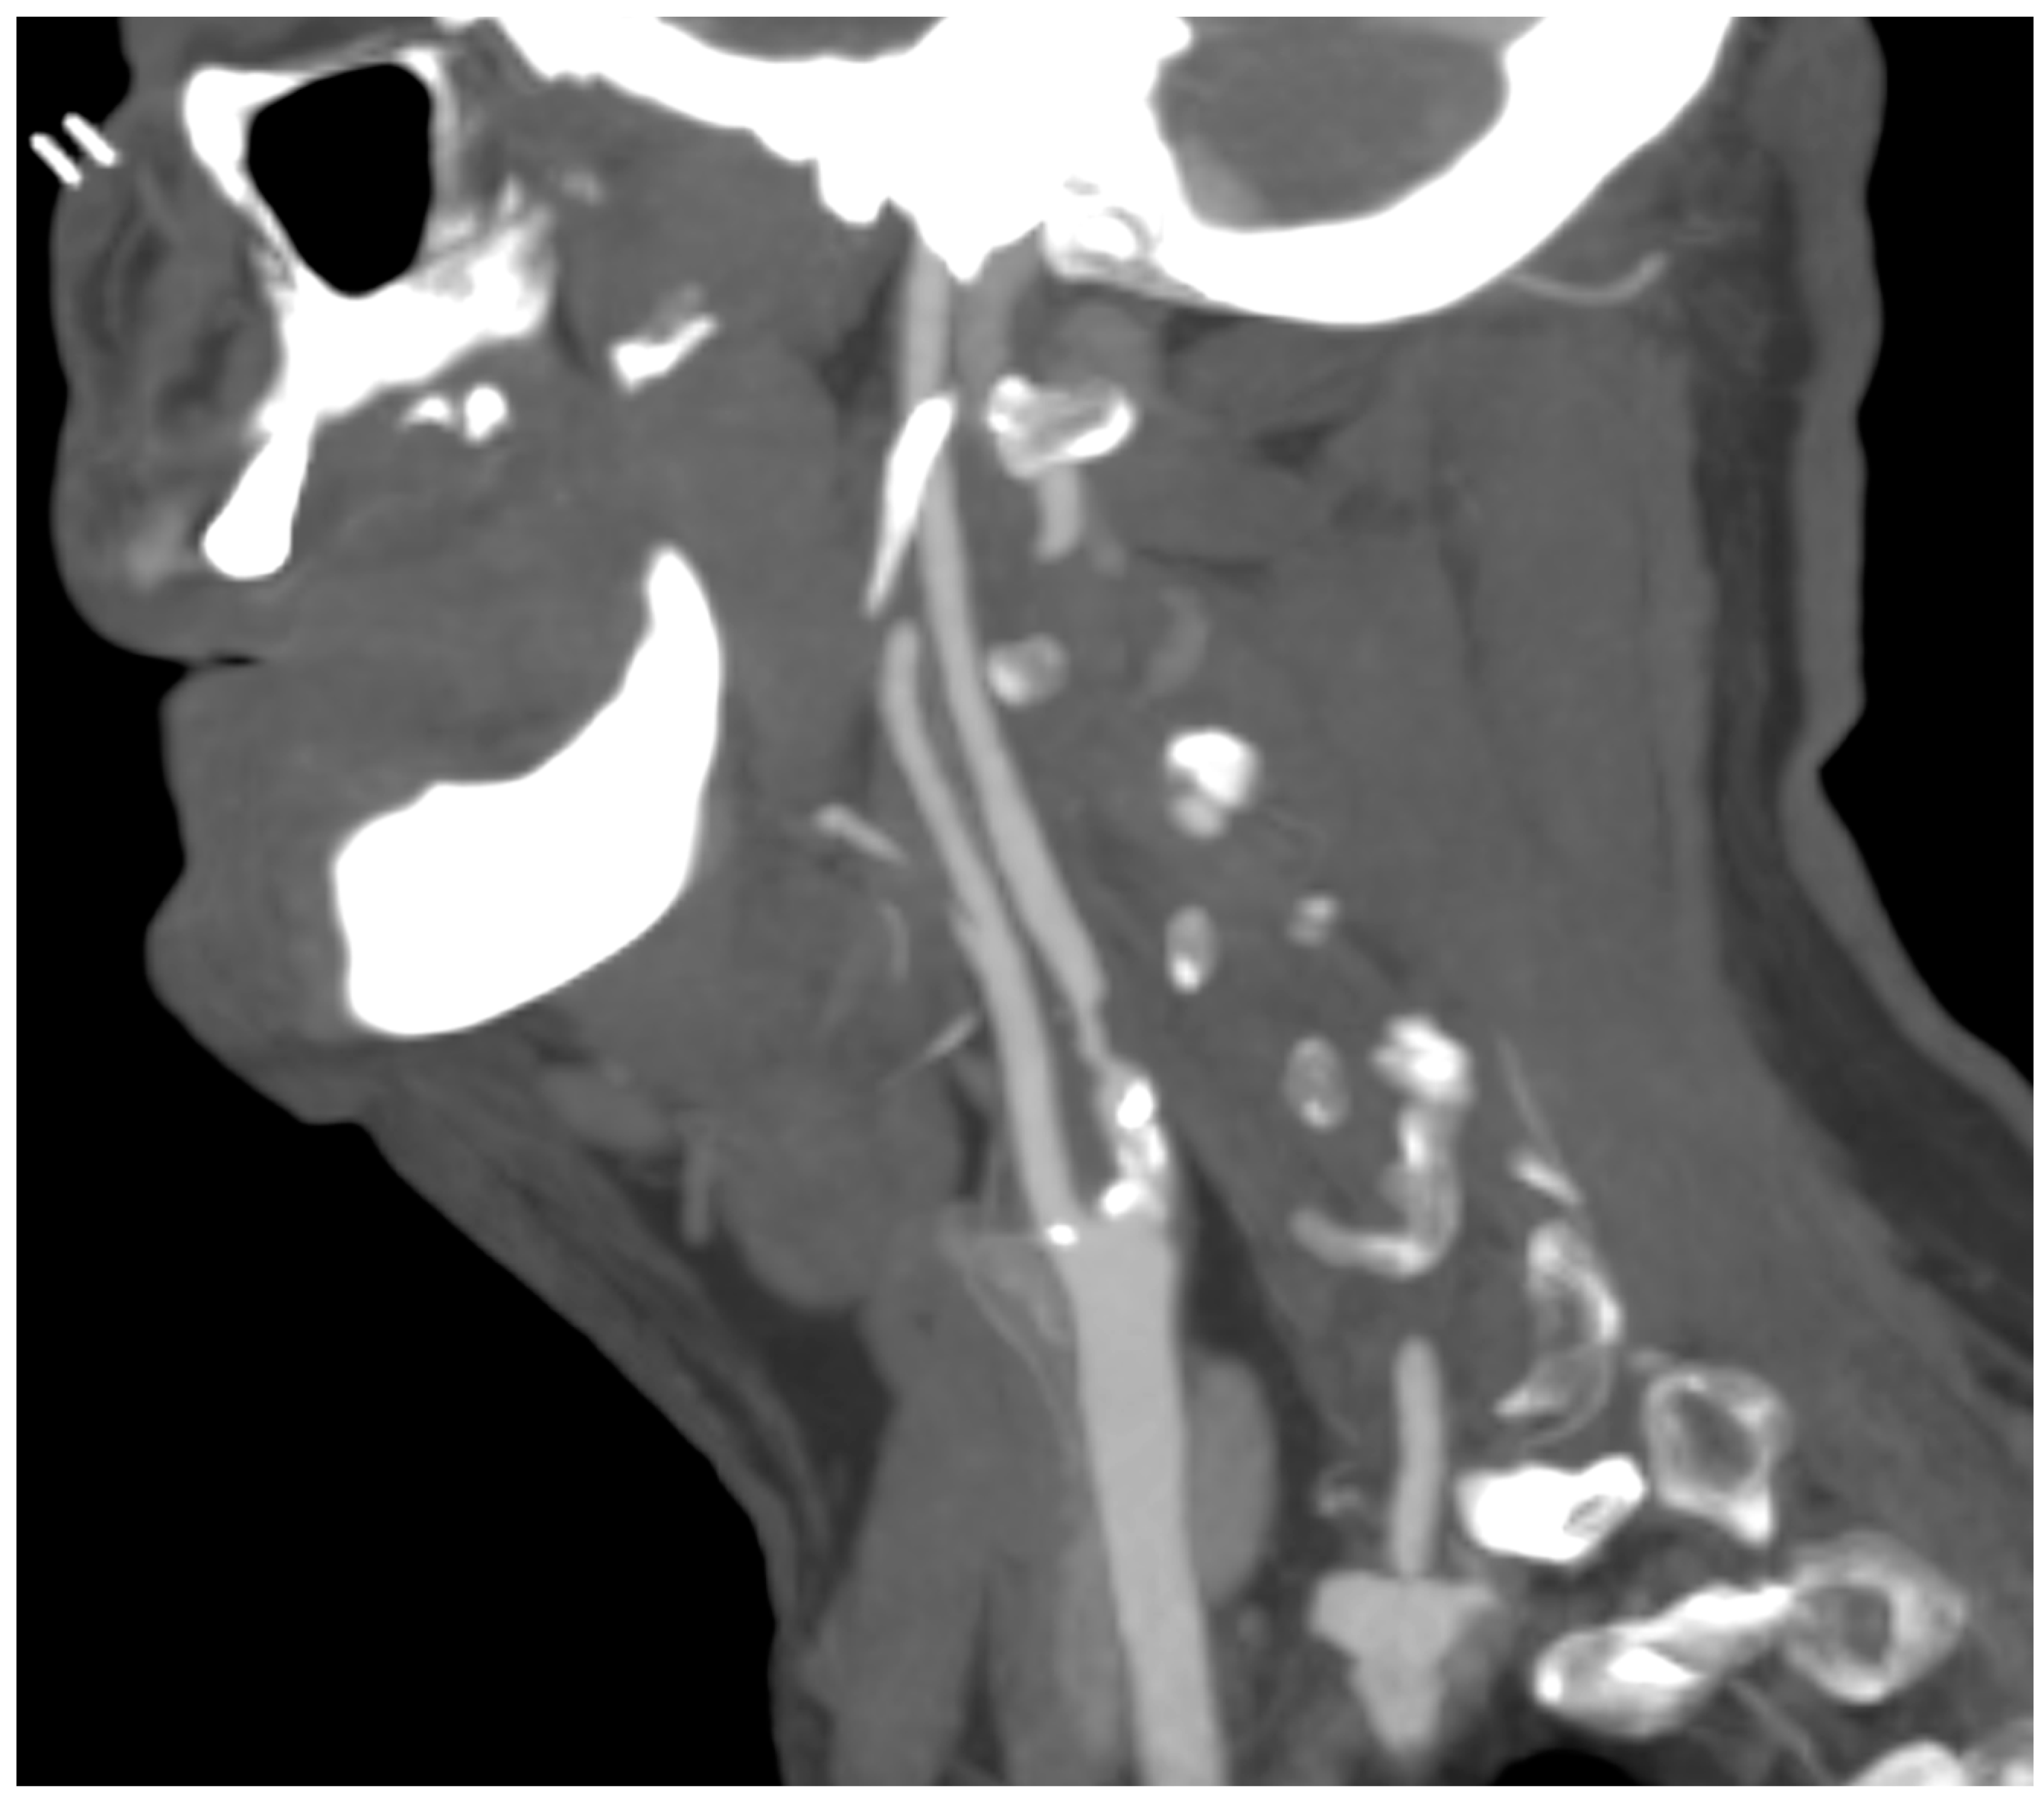

A computed tomography angiography (CT) was performed in patients presenting significative stenosis (>70%) according to DUS (Figure 3).

Figure 3.

CT angiography showing carotid plaque with significative stenosis.

In this study, the assessment of hemodynamically significant stenosis was completed with a cerebral CT scan and a CT angiography in the case of stenosis >70% in order to confirm and to objectively evaluate the plaque and its features. In the literature and in our experience, in addition to the degree of luminal stenosis, the plaque composition is also essential to evaluate and discuss. From mild fatty deposition in asymptomatic patients to complex, irregular plaques prone to the thromboembolism, DUS, CT scan, and high-resolution MR can provide significant information [34,35]. DUS is useful in determining hemodynamic features; Choi E. et al. report how CT scans help to assess the composition of plaque, with Hounsfield unit density and spotty calcium considered independent predictors of a greater risk of adverse cardiovascular event occurrence; Porambo ME et al. underline the ability of MR in the study of vulnerability plaque showing thoroughly lipid-rich necrotic core, thin/ruptured fibrous cap, and intraplaque hemorrhage, predicting factors of future stroke [36,37]. However, every imaging method can be a source of information about carotid plaques with DUS representing the first line of approach to CAAD, and CT scans and MR are useful tools to identify patients with high risk [38].